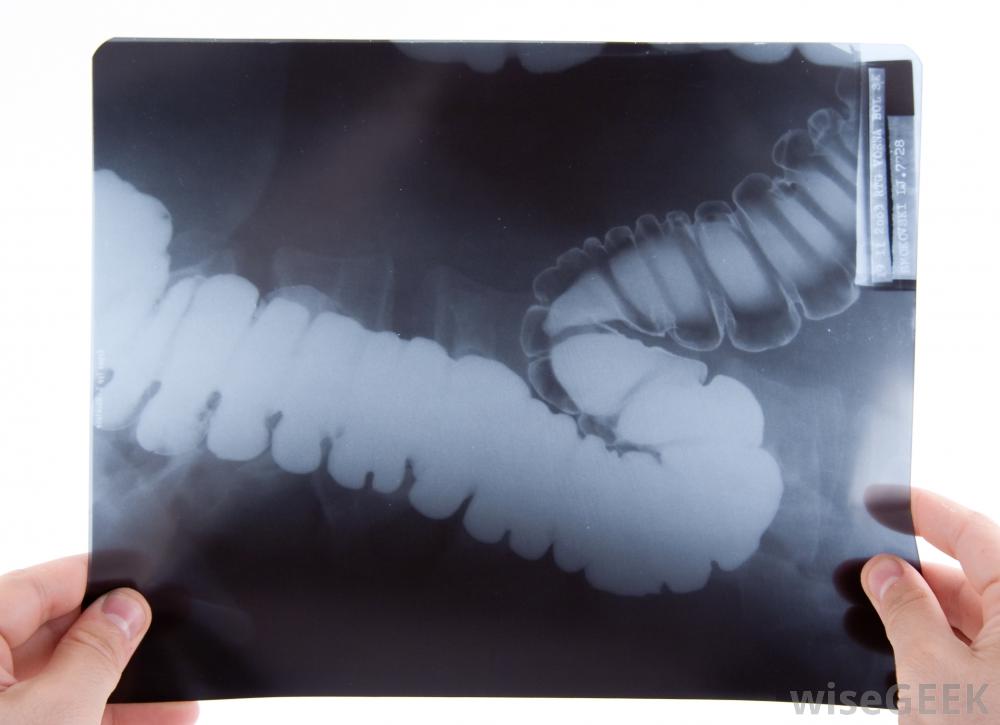

X光可用于观察肠道的特定区域当肠粘连严重时,可能导致完全梗阻,导致严重的腹部疼痛,有时是盆腔疼痛,无法排便,恶心或呕吐,发烧,最后可能引起肠道穿孔或其他肠管穿孔,这在医学上是很有可能引起肠穿孔或肠穿孔的

可以进行CT扫描,以确定是否有肠粘连。考虑到肠穿孔的风险,对于肠粘连或肠梗阻的说法,医生通常会非常重视。为了调查这一问题,可能会进行一些扫描,包括计算机断层扫描(CT)或磁共振成像(MRI)。更广泛的检查可以包括结肠镜检查或钡剂x光检查,以寻找特定的区域肠粘连或肠梗阻。